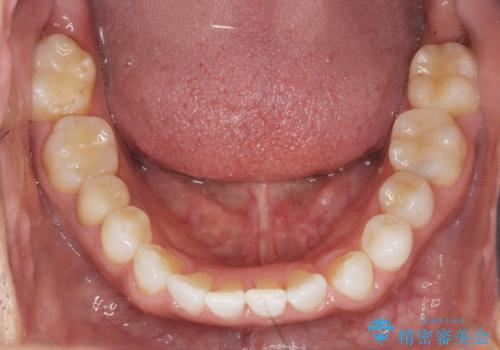

銀歯だらけの口の中を改善したい

- 83.6万円(仮歯・emaxインレー×8・ジルコニアクラウン×2)費用は治療当時の料金となります

見た目の改善だけではなく、長期的に虫歯の再発を防ぎ自分の歯を守るために銀歯をはずし、セラミック修復物・補綴物による機能回復を行いました。